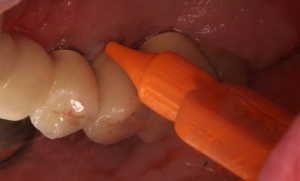

Diagnostische Parameter für die Beurteilung der dentalen und der periimplantären Zustände sind die Plaqueakkumulation, die Sondierungstiefen des Zahnes und des Implantates, Bluten auf Sondierung, Suppuration und der radiographische Knochenverlust (Salvi & Lang 2004). Unabdingbar ist im Minimum eine Sechspunktmessung (Sondiertiefen und klinischer Attachmentlevel). Immer wieder hört man von der Befürchtung, dass durch ein Sondieren des Implantates dieses geschädigt wird. In einer histomorphometrischen Studie an Hunden haben Etter et al. (2002) die Heilung des periimplantären Weichgewebes nach standardisiert klinischem Sondieren untersucht. Die Heilung des Epithelansatzes nach Sondierung des gesunden periimplantären Gewebes ist nach fünf Tagen abgeschlossen. Erfahrungsgemäß ist bei besonders aufmerksamem und vorsichtigem Sondieren ein äußerst geringes Verletzungsrisiko gegeben. Auch diese Techniken können in einem Praktikum bei einem Parodontologen aufgefrischt werden.

Im Rahmen einer solchen Nachuntersuchung werden neben der Plaqueakkumulation die klinischen Parameter Sondiertiefe und klinischer Attachmentlevel (6-fach je Zahn / Implantat), Bluten nach Sondieren (BnS), Suppuration und gegebenenfalls der radiographische Knochenverlust (Salvi & Lang 2004) erfasst.